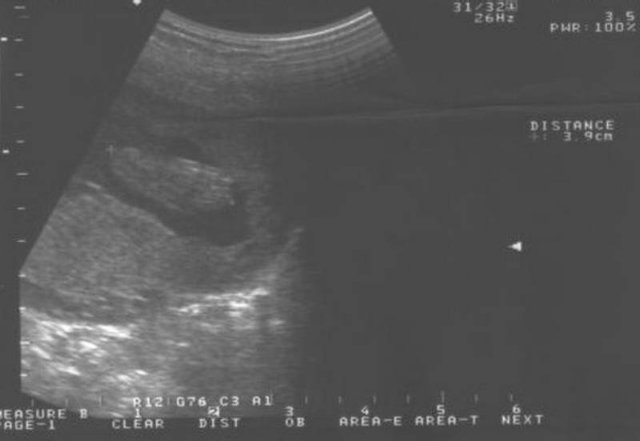

Hier streckt er sein Füsschen raus. 3,9cm ist der Fuss schon groß... 05. März 2004